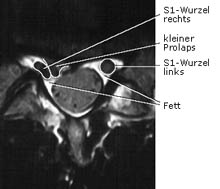

Relativ kleiner infradiskaler Prolaps mit Druck auf die rechte S1- Nervenwurzel, die im Vergleich zur gegenüberliegenden Seite abgeplattet erscheint. Der Wirbelkanal ist normal weit und epidural von ausreichend Fett (hell) ausgefüllt. Durch Abschwellen der Nervenwurzel und Schrumpfen des Prolaps bestehen gute Aussichten für einen Erfolg durch nichtoperative Maßnahmen, wie z. B. durch eine epiduralperineurale Injektion.